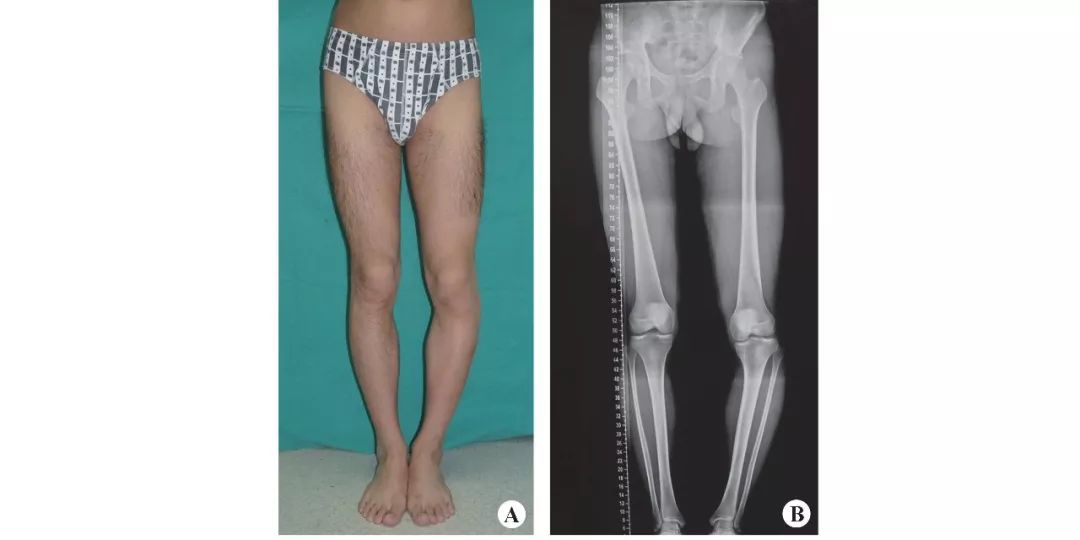

A 术前双下肢正面观;B 术前双下肢全长片;C 术前膝关节片;D 术前畸形分解确定CORA(蓝色圆圈),并草拟开口截骨区(白色斜线区);E 术后膝关节片,开口截骨的皮质骨铰链位置位于CORA的tBL上;F术后双下肢全长片;G术后外观